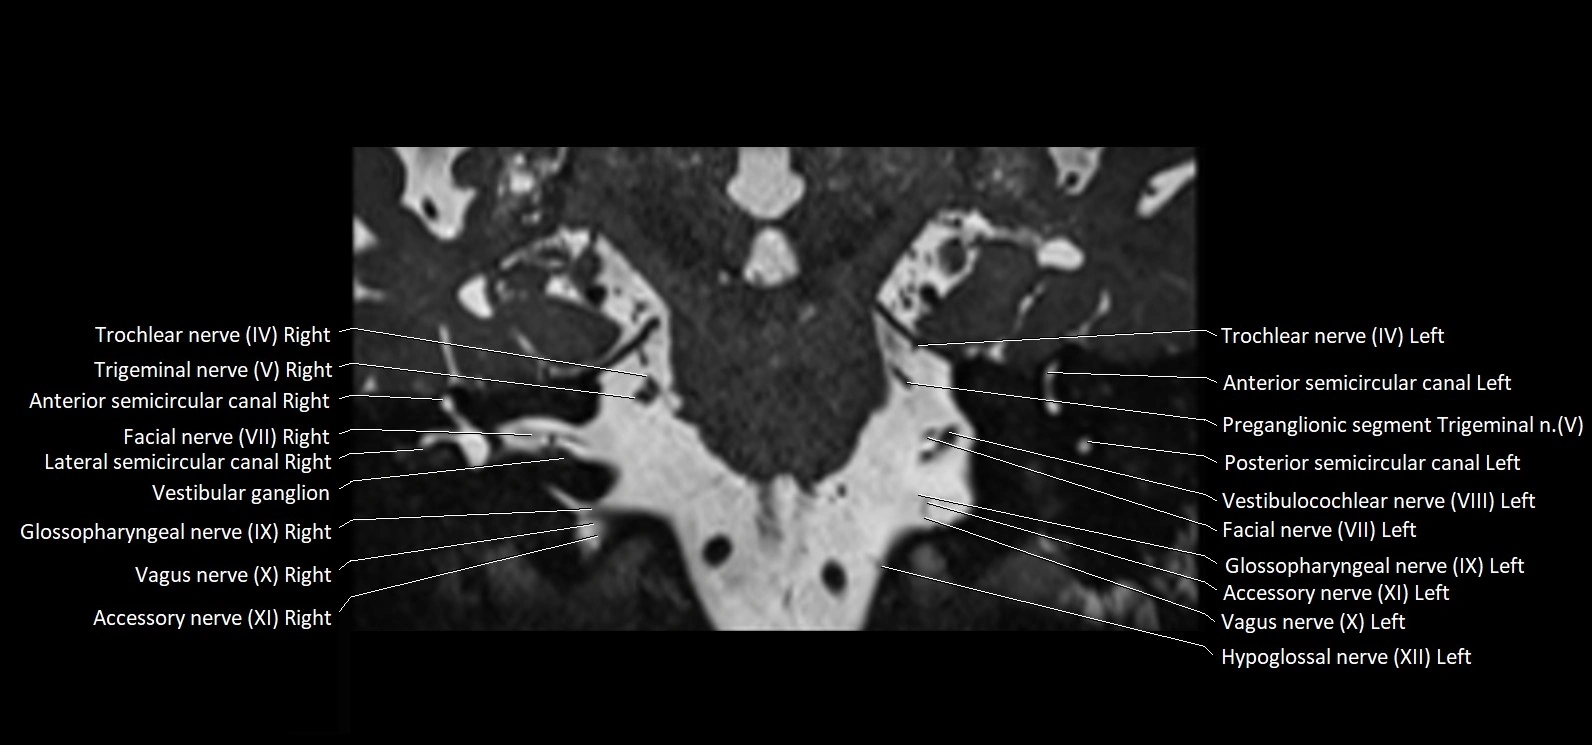

MRI images

image